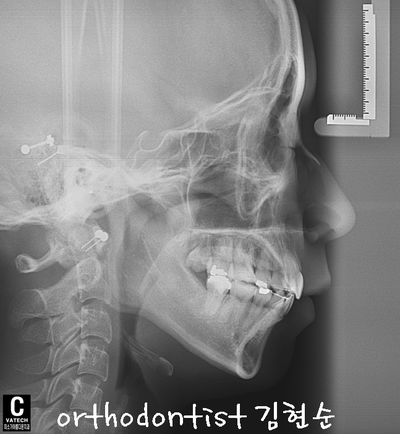

Chief Complaint

Treatment plan.